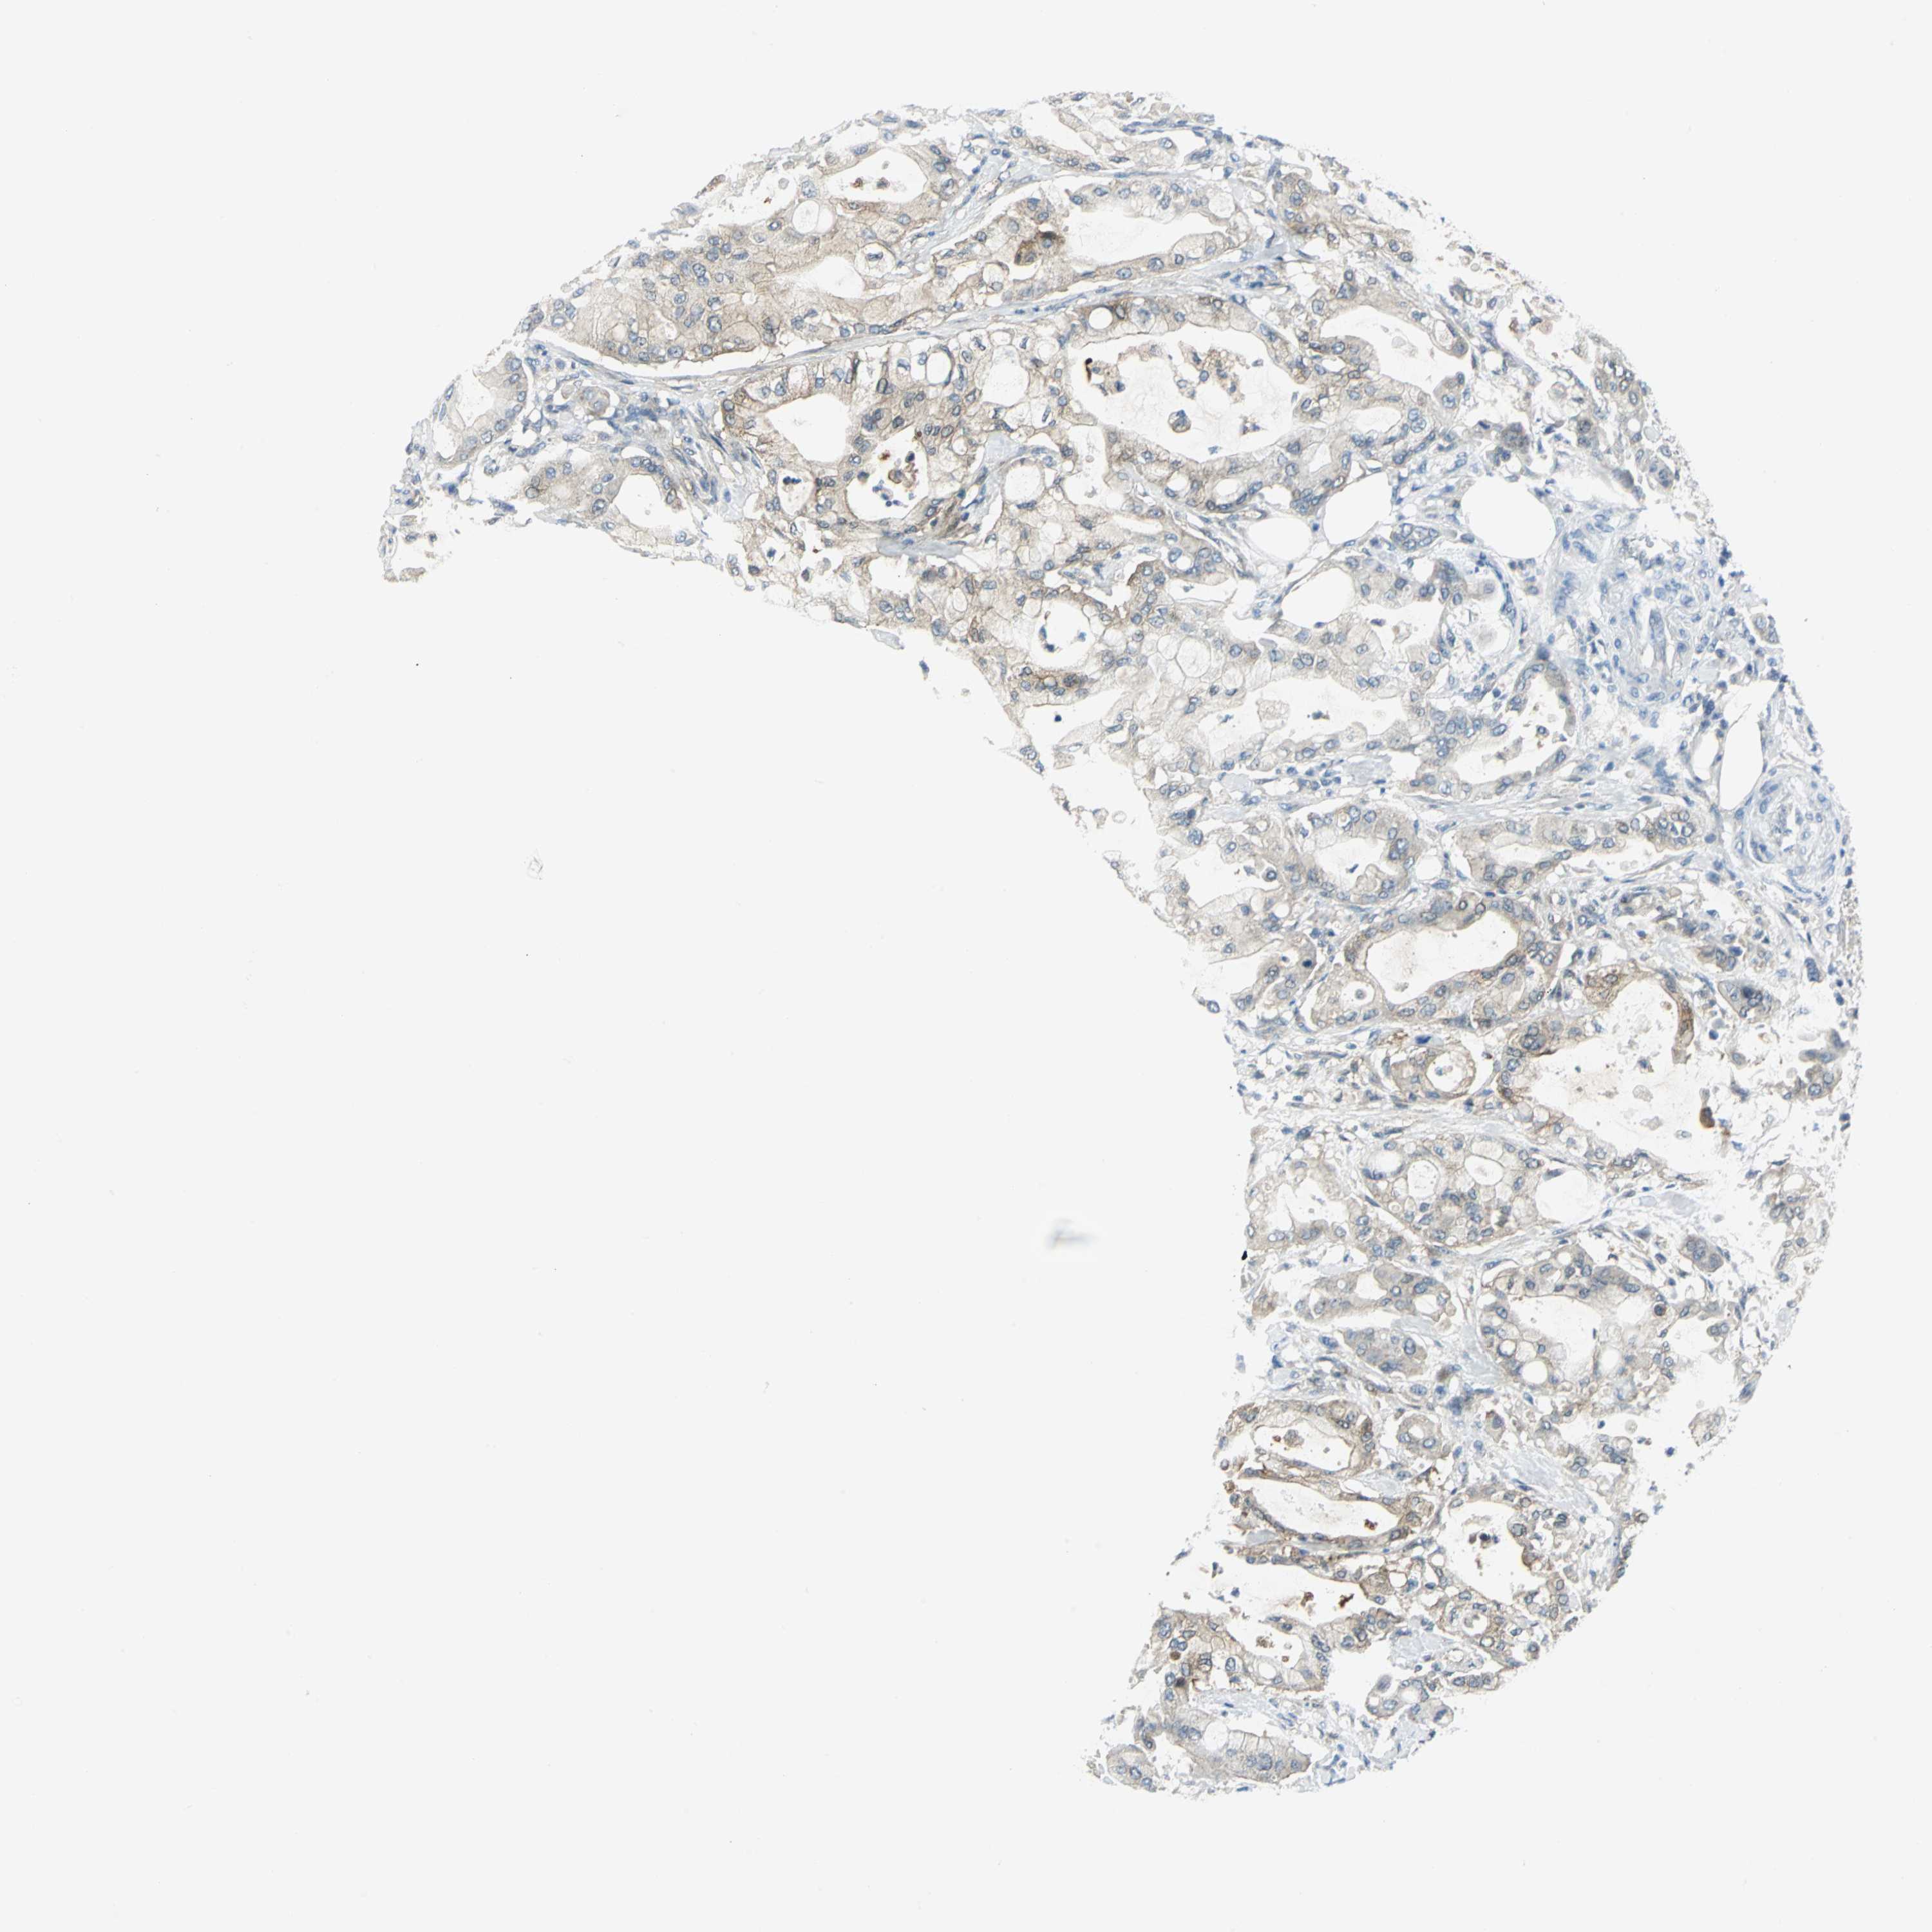

PANCREATIC CANCER - Protein expressioni

A mouse-over function shows sample information and annotation data. Click on an image to view it in a full screen mode. Samples can be filtered based on level of antibody staining by selecting one or several of the following categories: high, medium, low and not detected. The assay and annotation is described here.

Note that samples used for immunohistochemistry by the Human Protein Atlas do not correspond to samples in the TCGA dataset.

Antibody stainingi

Antibody staining in the annotated cell types in the current human tissue is reported as not detected, low, medium, or high, based on conventional immunohistochemistry profiling in selected tissues. This score is based on the combination of the staining intensity and fraction of stained cells.

Each image is clickable and will lead to virtual microscopy that enables deeper exploration of all samples and also displays staining intensity scores, fraction scores and subcellular localization as well as patient and tissue information for each sample.

Antibody HPA004177

Antibody CAB006252

Staining

High

Medium

Low

Not detected

Intensity

Strong

Moderate

Weak

Negative

Quantity

>75%

75%-25%

<25%

None

Location

Nuclear

Cytoplasmic/membranous

Cytoplasmic/membranous,nuclear

Adenocarcinoma, NOS

Adenocarcinoma, metastatic, NOS